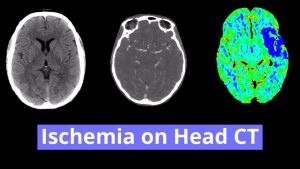

Diagnosis

- Basilar artery thrombosis

Large area of hypoattenuation in the right hemipons extending superiorly into the ipsilateral cerebral peduncle concerning for acute/early subacute infarct. No evidence of substantial associated mass effect or hemorrhagic transformation.

Hyperattenuating appearance of the basilar artery, concerning for thrombosis.